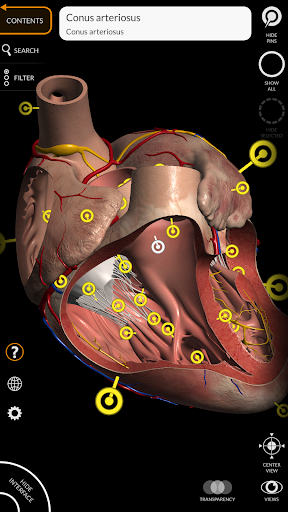

يتيح لك "Anatomy 3D Atlas" دراسة التشريح البشري بطريقة سهلة وتفاعلية.

من خلال واجهة بسيطة وبديهية، من الممكن ملاحظة كل بنية تشريحية من أي زاوية.

تتميز النماذج التشريحية ثلاثية الأبعاد بتفاصيل خاصة ودقة تصل إلى 4K.

يسهل التقسيم حسب المناطق والمناظر المحددة مسبقًا مراقبة ودراسة الأجزاء الفردية أو مجموعات الأنظمة والعلاقات بين الأعضاء المختلفة.

• الجهاز القلبي الوعائي

• من خلال تحديد نموذج أو دبوس، يظهر المصطلح التشريحي ذي الصلة

• وصف العضلات: الأصل والإدخال والتعصيب والعمل